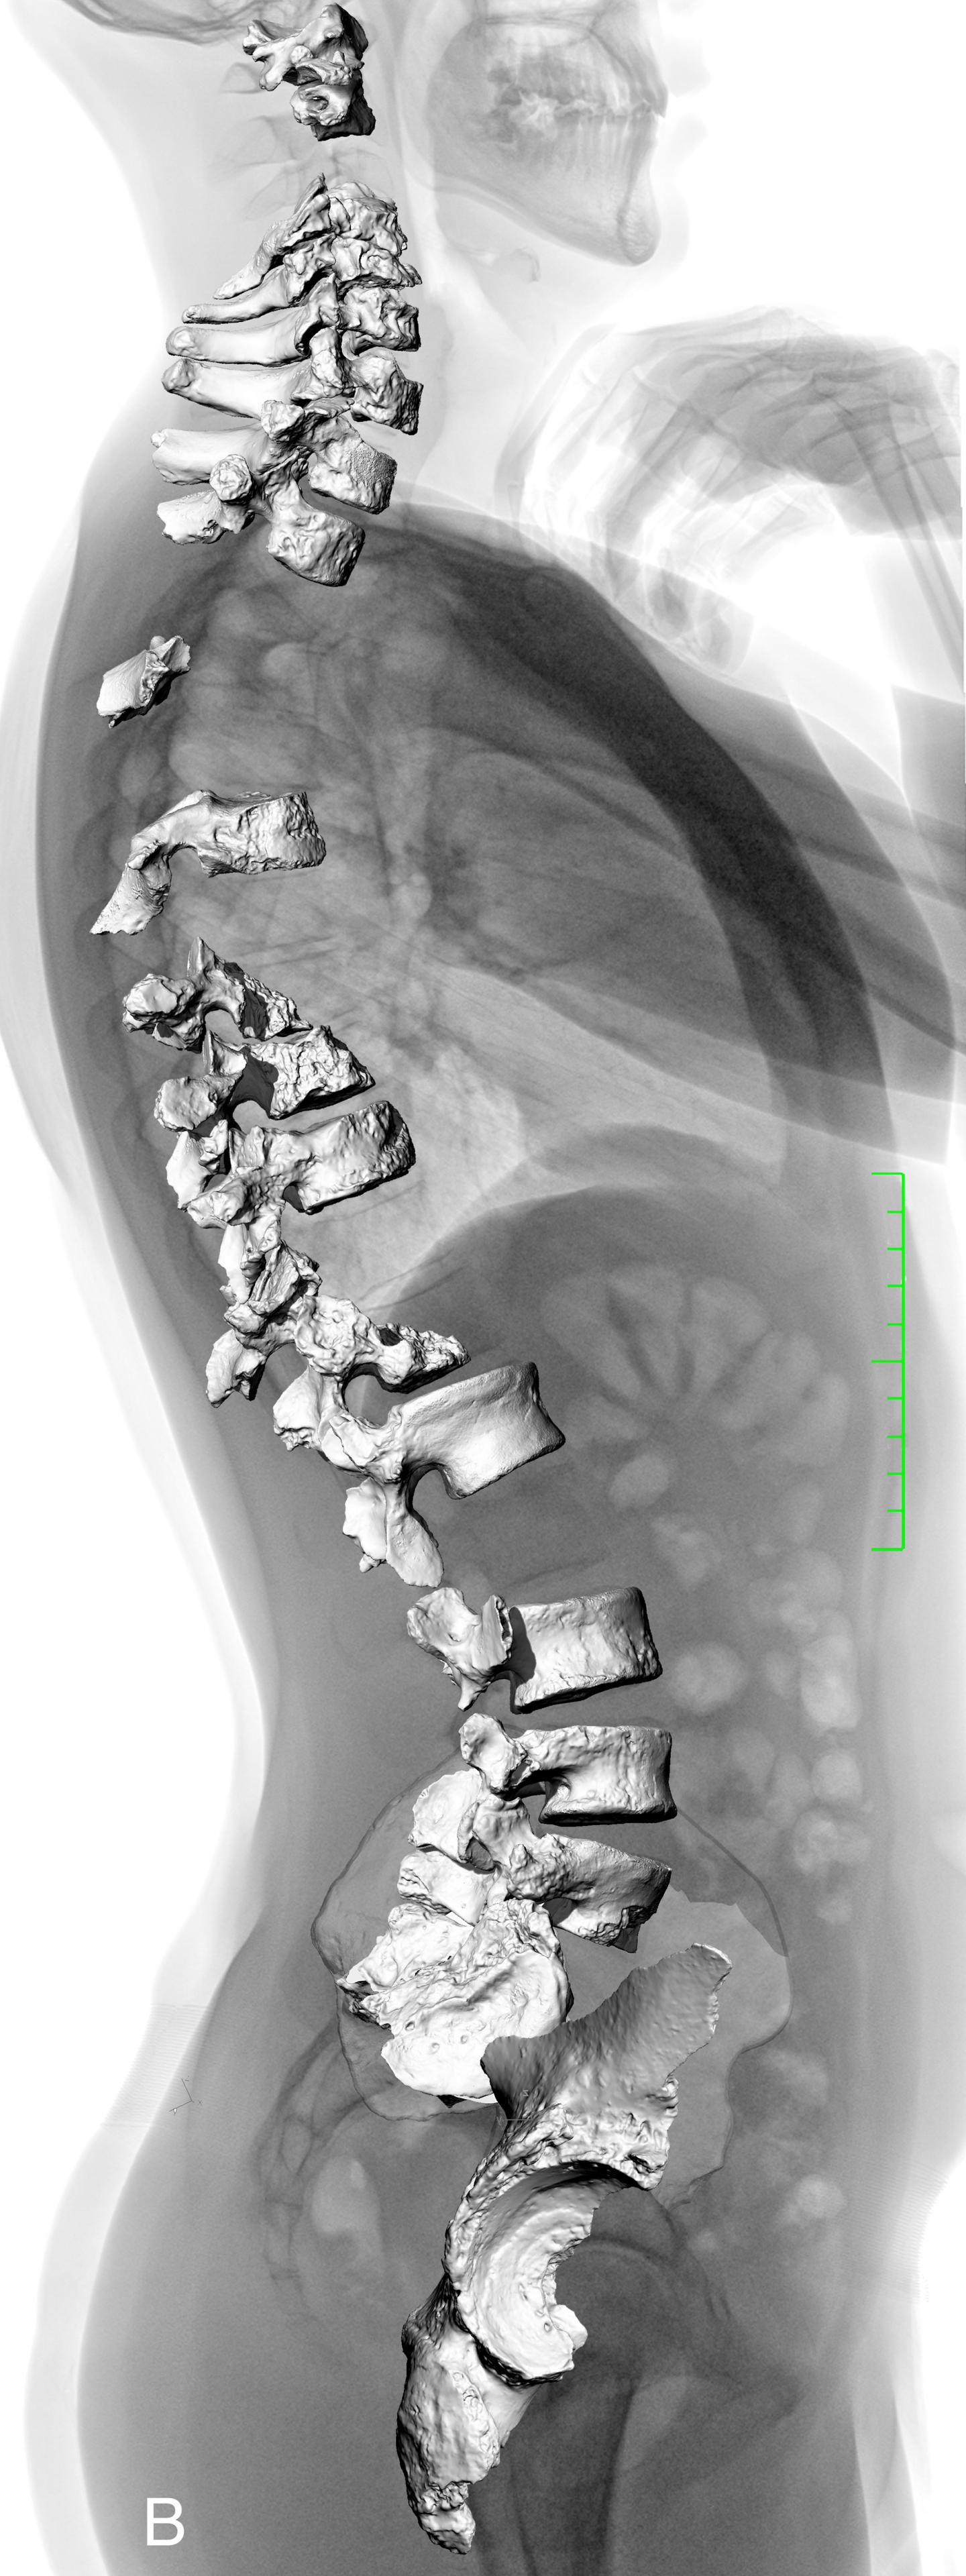

Researchers report a reanalysis of the vertebrae and pelvis of a Neandertal individual that indicates spinal curvatures similar to those of modern humans. Reconstructions of Neandertal posture have varied, with early reconstructions depicting Neandertals as hunched and incompletely upright and recent studies suggesting that Neandertals' spinal curvatures were flatter than those of modern humans. Martin Haeusler, Erik Trinkaus, and colleagues reassessed the vertebral remains of the La Chapelle-aux-Saints Neandertal individual, using a pelvic reconstruction to infer angles of curvature of the individual's spine. Considering the likely osteoarthritis and other age-related degenerations of the individual, the authors examined both the angle of the pelvis in relation to the spine and the articulations of the cervical and lumbar vertebrae. Both lines of evidence suggest that the spinal curvature of the individual was within the range of normal modern human posture, excepting the effects of disease. The findings are corroborated by other Neandertal individuals. According to the authors, the results suggest that previous interpretations that Neandertal anatomy is functionally different from modern humans may be inaccurate and that Neandertal anatomy and behavior were likely similar to those of modern humans.

Article #18-20745: "Morphology, pathology, and the vertebral posture of the La Chapelle-aux-Saints Neandertal," by Martin Haeusler et al.